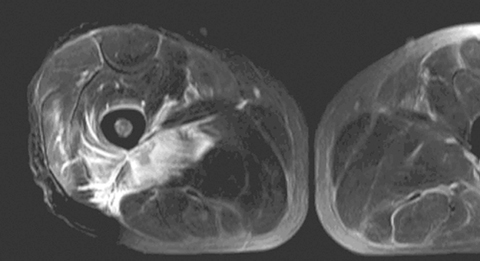

MRI helped in making the diagnosis and delineating the extent of the muscle involvement in all patients, as (see Box 2) the high signal intensity of the pathological process (prolonged T2) can be easily distinguished from the relatively low signal intensity of normal muscle (shortened T2). The superiority of MRI for differentiating pyomyositis from other pathological processes, outlining the extent of involvement and localising fluid collections, has been previously reported.8 The ability of MRI to obtain multiplanar contiguous sections provides excellent anatomical detail of each muscle group and precisely locates the site of disease. MRI scans in 43 cases of pyomyositis found that hyperintense signals on T2-weighted images were detected in all patients.18 A hyperintense rim on unenhanced T1-weighted images and peripheral enhancement after gadolinium injection was useful for identifying the number, size and location of soft tissue abscesses.18